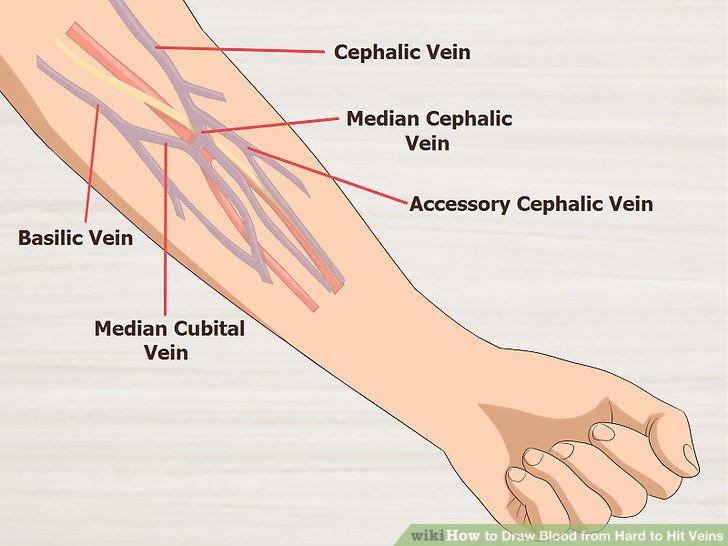

Diagram Of Veins In Arm For Phlebotomy

schematron.org

schematron.org

veins blood arm draw phlebotomy diagram hard hit cubital cephalic median step fuller steps proper area below use green